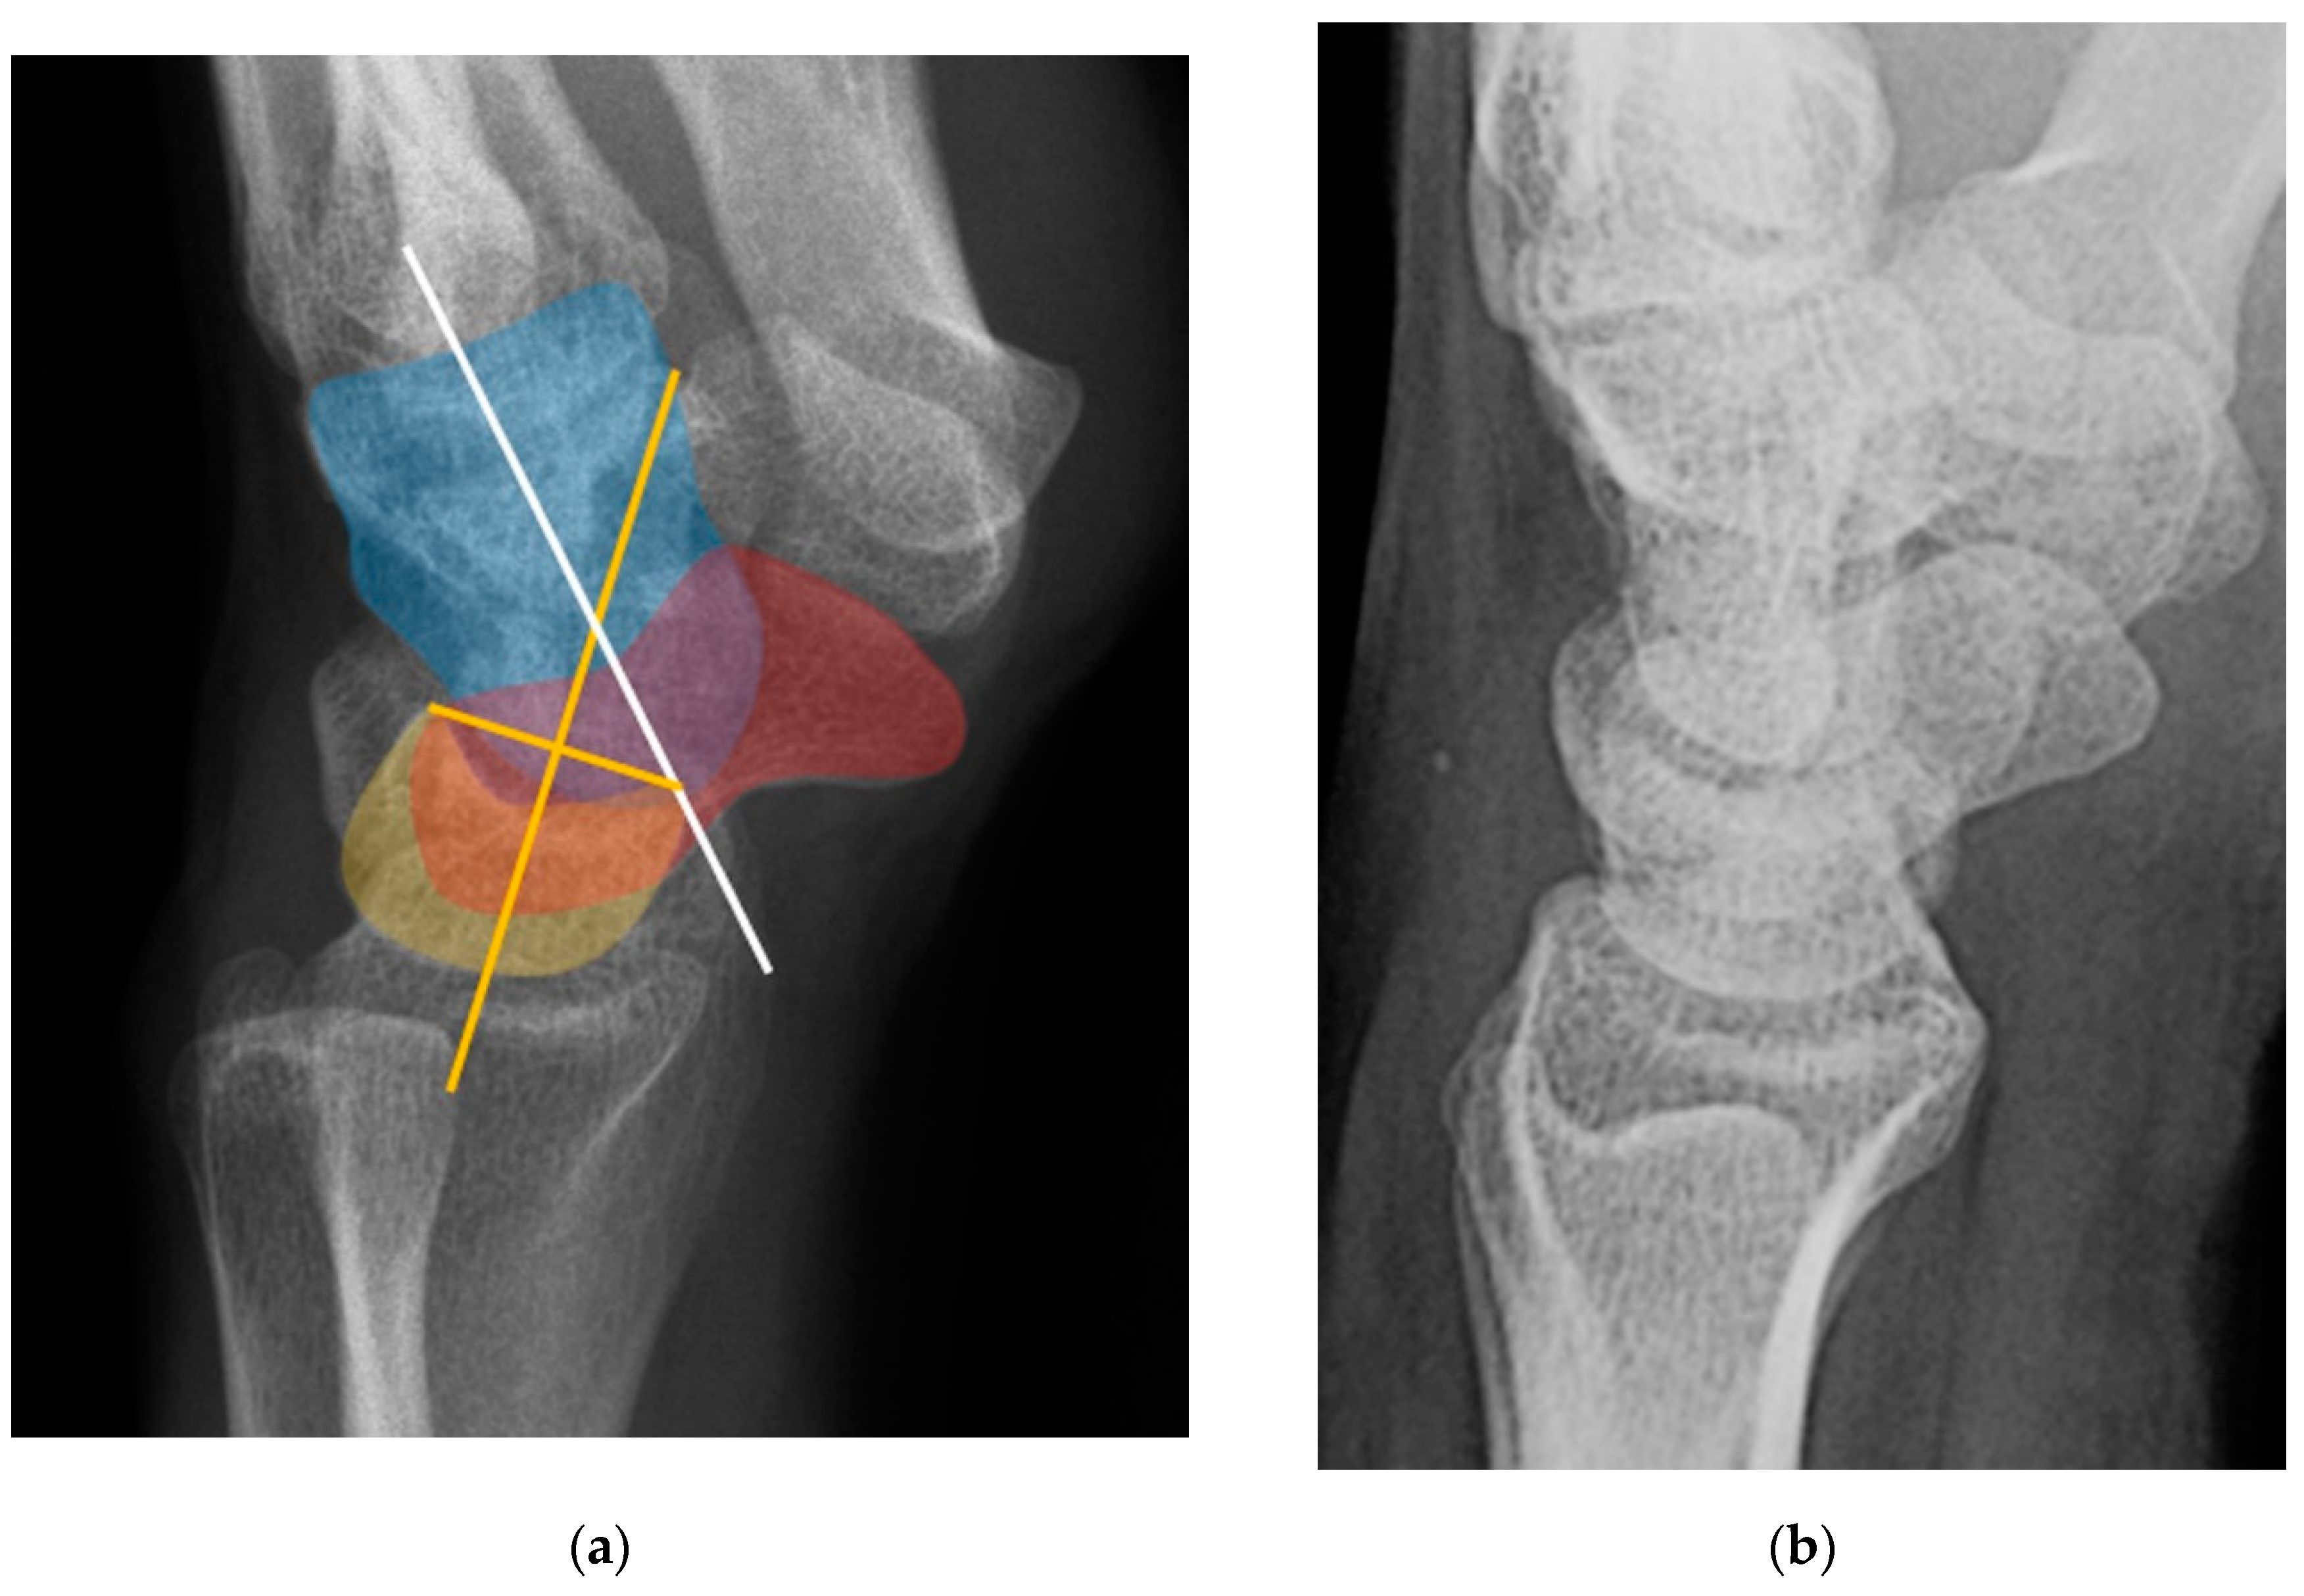

Figure 32. (a) Lateral wrist radiograph with overlay showing excessive volar rotation of the scaphoid relative to the lunate, with an increased scapholunate angle to nearly 90°. The red line is drawn along the volar surface of the scaphoid while a yellow line is drawn through the lunate axis; (b) Normal lateral wrist radiograph for comparison.